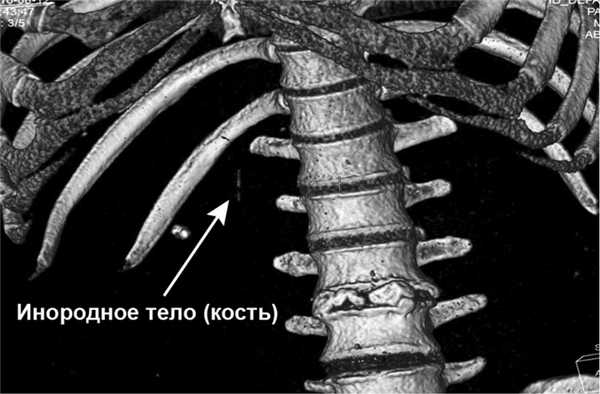

Результаты лабораторных исследований: лейкоциты (WBC) 11,7·10 9 /л; гемоглобин (HGB) 134 г/л, биохимический анализ крови — без отклонений от нормы. Начато проведение антибактериальной терапии (ципрофлоксацин 400 мг 3 раза в день в/в, метронидазол 500 мг 3 раза в день в/в). Учитывая неясный генез образования абсцесса, с целью дообследования была выполнена КТ органов брюшной полости с в/в болюсным усилением, по результатам которого выявлено инородное тело, располагающееся в передней стенке выходного отдела желудка (рис. 1, 2), размерами 30×2 мм с пенетрацией в паренхиму S3 печени и формированием абсцесса 45×35×30 мм (рис. 3, 4).

Рис. 2. Пациент П. КТ органов брюшной полости с 3D-реконструкцией. Визуализируется инородное тело.